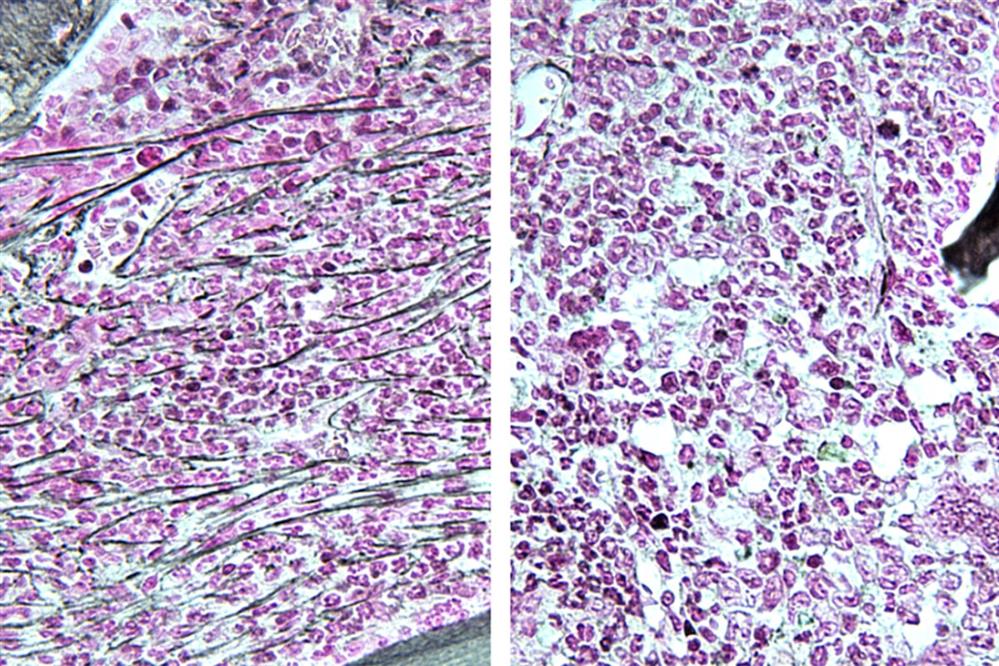

Στη φωτογραφία αποτυπώνεται ο μυελός των οστών ενός ποντικού με μυελοϋπερπλαστικό νεόπλασμα (αριστερά), ο οποίος παρουσιάζει ίνωση ή ουλώδη ιστό (οριζόντιες γραμμές). Ένα ποντίκι με την ίδια ασθένεια που υποβλήθηκε σε θεραπεία με αναστολέα RSK1 παρουσιάζει μυελό των οστών που μοιάζει φυσιολογικός (δεξιά).